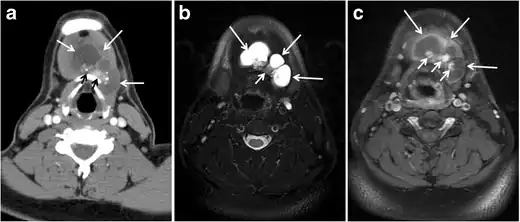

Fig. 6. A 61-year-old female patient with locally aggressive PTC. an Enhanced axial CT scan of the neck demonstrates a heterogeneous infiltrative thyroid mass. This mass diffusely involves the entire gland and circumferentially encases the trachea with involvement of bilateral tracheoesophageal grooves (white arrows). b, c Additional axial cranial images show right cricoid cartilage destruction (black arrows in b), right thyroid cartilage destruction (black arrow in c), right vocal cord paralysis (white arrows in b), and bilateral cervical lymphadenopathy (arrowheads).[1]

Finally, the possibility of metastatic disease should be excluded. PTCs and medullary thyroid carcinomas tend to metastasize to regional lymph nodes. According to the AJCC/UICC TNM staging system, the nodal stage is classified by site: N1a indicates level VI nodal involvement, including paratracheal nodes; N1b indicates unilateral or bilateral lateral cervical nodal disease or superior mediastinal nodal disease (Figs. 4, 55 and and6)6).[1]